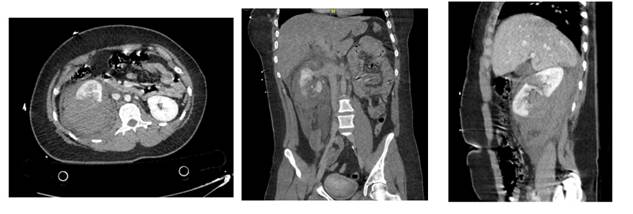

Case 2

A 55-years-old male with no medical history, presented to de ER with left chest and abdominal pain after being crashed by a car while riding an e-scooter at 15km/h on a crosswalk. Physical examination centered pain mostly on the ribs, with tender abdomen and no pain while its palpation. The CT scan showed a left pneumothorax, lingula contusion, two broken left ribs, and a subcapsular hematoma of the left kidney (Figure 3 & 4), being classified as an AAST grade III, the patient was hospitalized for close vigilance, and maintained stable throughout the whole admission with normal GFR and hemoglobin, receiving a conservative management. The follow up CT scan showed resolution of lesions.